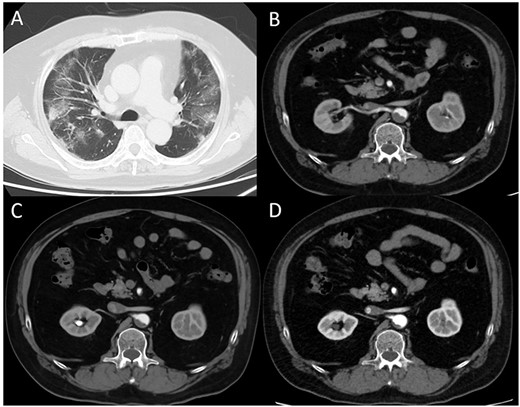

A 62-year-old man with aggravated symptoms of fever, cough and malaise for 12 days was admitted to the hospital. The patient was obese, with a body mass index of 30.0. The patient was conscious but presented with laboured breathing. His body temperature was 36.7 C, blood pressure was 121/62 mmHg, heart rate was 84/min respiratory rate was 24/min and oxygen saturation was 82% with room air. Non-enhanced computed tomography (CT) showed inflammation in the total lung field (Fig. 1A). Blood test results revealed increased levels of D-dimer of 23.4 mg/L, C-reactive protein of 1600 nmol/L and creatinine of 150.3 μmol/L. The result of SARS-CoV-2 polymerase chain reaction detective kit (TAKARA BIO INC., Shiga, Japan) was positive with N501Y mutation. He was subsequently admitted to the hospital and received oxygen inhalation and intravenous injections of remdesivir, dexamethasone and unfractionated heparin. On the following day, the patient complained of pain and cold sensation in his left leg upon waking. Emergency enhanced CT showed a thrombus in the aorta at the juxtarenal level (Fig. 1B) and an obstructed left iliac artery with a thrombus (Fig. 2A). No cardiac thrombi were observed. The activated partial thromboplastin time was 28 s, and the D-dimer level was unchanged from the previous day, as shown in Fig. 3. Other blood test results showed normal values, including antinuclear antibodies and markers of vasculitis or malignancy.

(A) Computed tomography (CT) image obtained on the first day. The bilateral lungs showed inflammation. (B) Enhanced CT image obtained immediately after developing acute limb ischemia. Intra-aortic thrombus was observed at the juxtarenal level. (C) Enhanced CT image obtained on post-operative day 11. The thrombus size had decreased. (D) Enhanced CT image obtained 1 month after surgery. The thrombus had further diminished.

The patient underwent urgent thrombectomy to salvage the left lower limb. Using a Fogarty catheter, fresh thrombus in the left iliac artery and superficial femoral artery was removed. The patient’s hypoxia condition continued until post-operative day 4. From post-operative day 6, coumadin was initiated to treat the remaining thrombus in the aorta (Fig. 1C). After confirming a negative test result for COVID-19, the patient was discharged on post-operative day 20. A month after the surgery, repeat enhanced CT showed a decrease in the quantity of intra-aortic thrombus (Fig. 1D) and the patent left iliac artery (Fig. 2B).